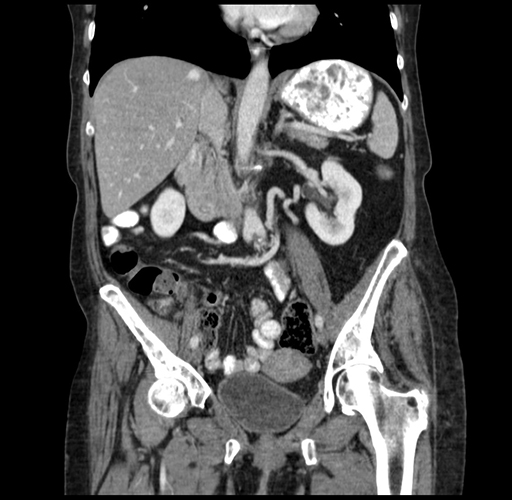

Pre-Chemo: Coronal Venous

Coronal Venous